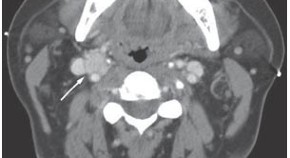

• Tubercular lymphadenitis of the cervical lymph nodes can be easily confused with node metastases. Chaturvedi et al. present the case of a 66-year-old man who was diagnosed with tongue carcinoma. PET–CT imaging suggested extensive neck-node metastases but frozen sections revealed tuberculosis of the neck nodes. The patient underwent surgery and received multidrug antitubercular therapy. The need for cautious interpretation of PET–CT reports, especially in tuberculosis-endemic areas, is discussed.